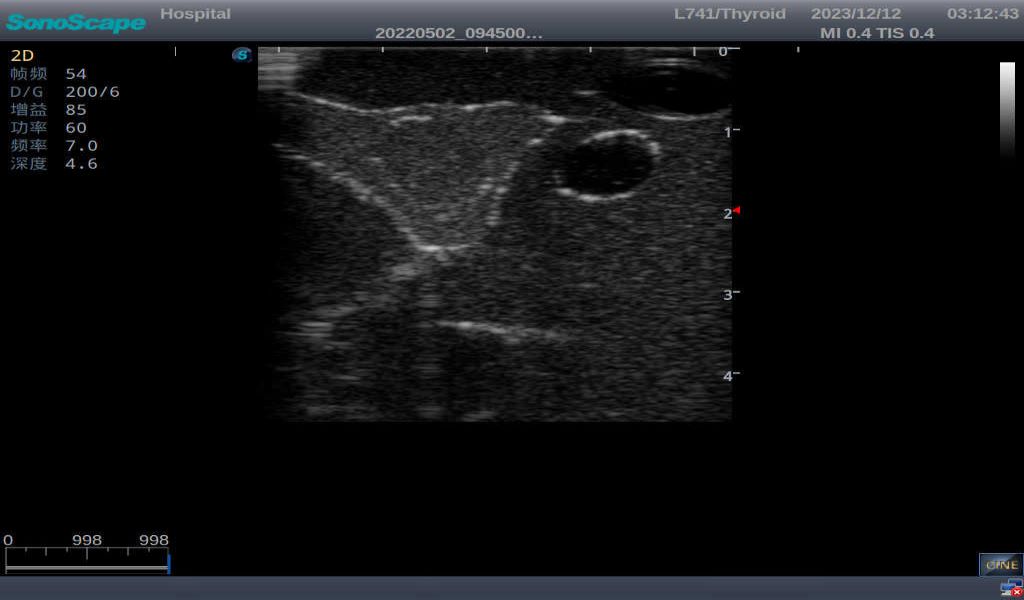

3) It comes with four (4) thyroid modules and can show five (5) ultrasonic images: normal thyroid, thyroid adenoma, thyroid cancer, nodular goiter, thyroid cyst

Thyroid cyst, which fluid area, dark and echo-free area can be seen